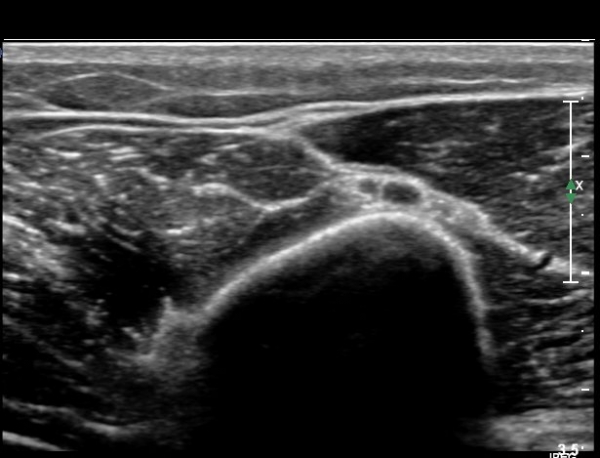

¿ä°ñ °í¶û ¸»´Ü¿¡¼­ ¿ä°ñ½Å°æ Á¾´Ü¸é°Ë»ç»ó ¿ä°ñ½Å°æÀÇ Àú¿¡ÄÚ ºÎÁ¾°ú Áß°£ ºÎÀ§¿¡

±¹¼ÒÀû ÇùÂøÀÌ °üÂûµÈ´Ù(»çÁø 5).